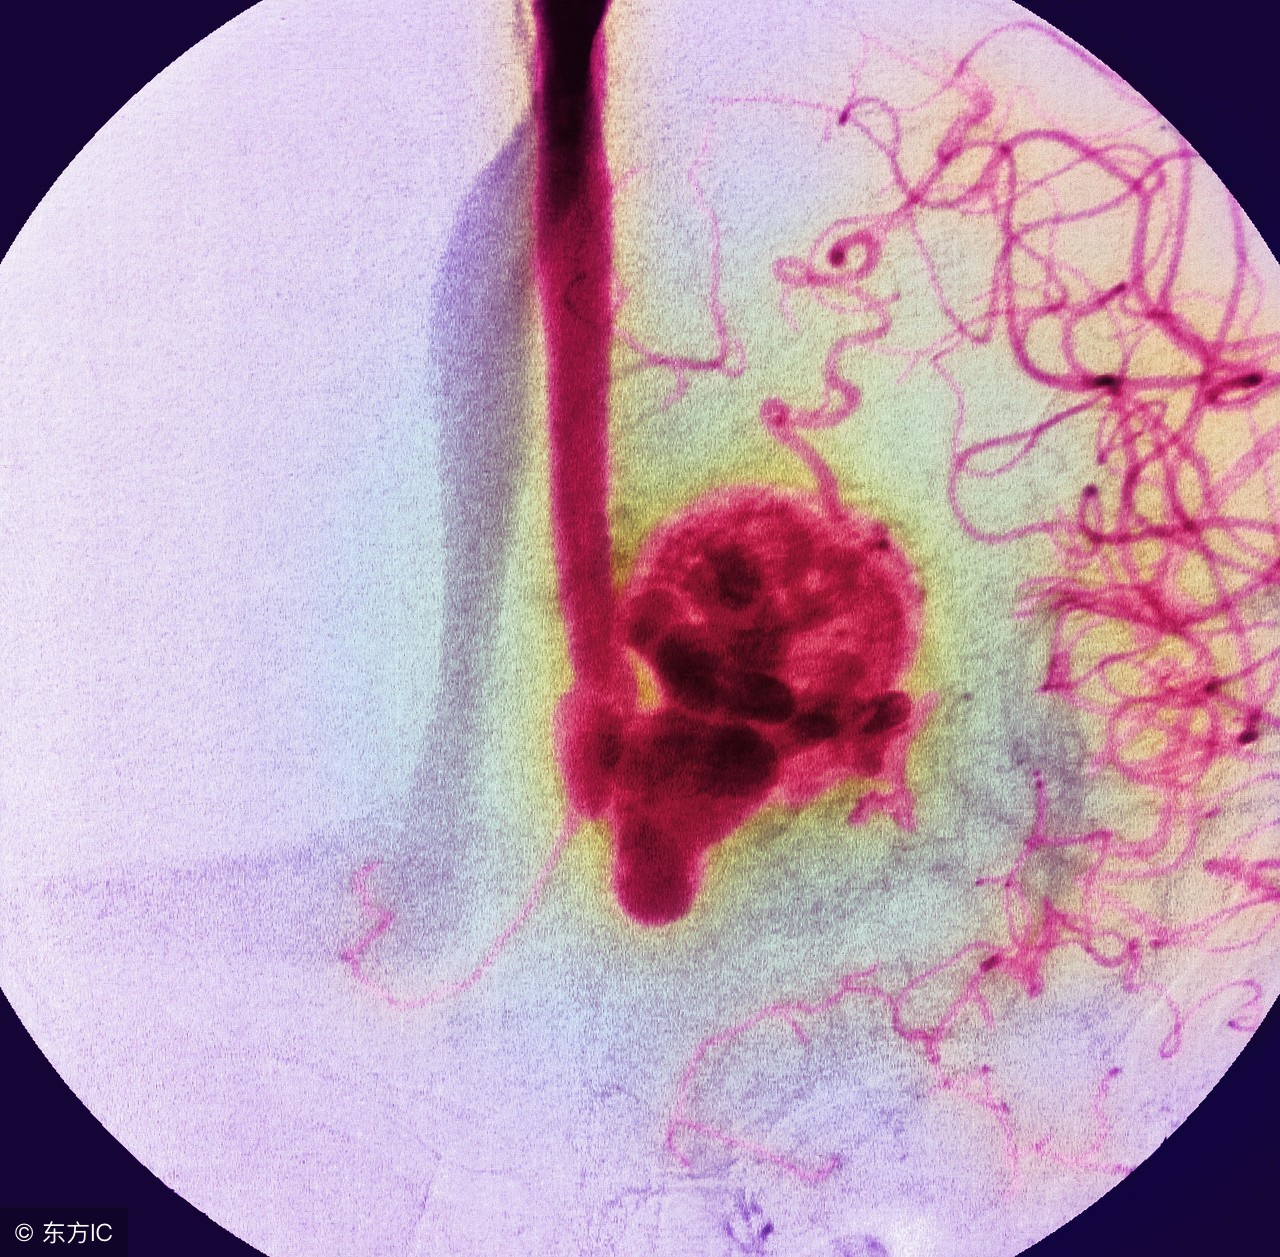

血管瘤是由胚胎期间成血管细胞增生而形成的常见于皮肤和软组织内的先天性良性肿瘤或血管畸形,多见于婴儿出生时或出生后不久。残余的胚胎成血管细胞,活跃的内皮样胚芽向邻近组织侵入,形成内皮样条索,经管化后与遗留下的血管相连而形成血管瘤,瘤内血管自成系统,不与周围血管相连。

超导介入治疗血管瘤包括超导光波介入、超导射频介入、超声微介导方法,是在超声的引导下根据具体的病情选择用光波、射频、药物等方法或几种方法综合治疗.其治疗血管瘤的原理是将头发丝粗细的微导管穿刺到引起异常结构的营养支管腔及膨大处,利用超声定位将光波、射频、药物等导入病变组织,使其阻断瘤体的营养供应,同时改变细胞生存的内部环境,血管瘤内壁腔隙及毛细血管瘤腔内大量血栓形成,最后导致血管瘤内皮细胞失去活性,血管瘤逐渐消退,最后达到治愈的目的。